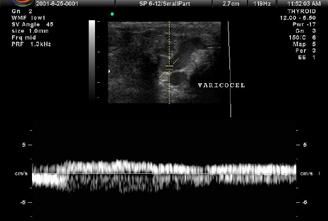

Diagnosticul clinic al MC se bazează pe următoarele 3 elemente clinice: comă profundă cu un scor Glasgow de 3, abolirea tuturor reflexelor trunchiului cerebral, absenţa respiraţiei spontane, după un test de hipercapnie. Cele două examinări paraclinice utilizate in completarea diagnosticului clinic de MC sunt angiografia-CT cerebrală multislice sau electroencefalograma (EEG). Dopplerul transcranian (TCD) este util pentru alegerea momentului realizării lor (1-4)

ACTMS trebuie efectuată: după o perioadă de 6 ore de la diagnosticul clinic, la un pacient stabil hemodinamic (media presiunii arteriale > 65 mmHg) (1) . Cronologic, oprirea sistemului circulator interesează in primul rând ramurile corticale ale arterele cerebrale medii, apoi ramurile proximale a poligonului Willis și în final circulaţia vertebro-bazilară. Efectul întârziat asupra circulației posterioare s-ar explica prin rolul protector al tentoriului cerebelului împotriva creșterii presiunii intracraniene. Absența opacifierii venelor cerebrale interne în ACT constituie cel mai precoce, mai sensibil și mai specific semn al MC demonstrând stopul circulator în etajul supratentorial (2)

• Studiul opacifierii ramurilor corticale ale arterelor cerebrale medii (M4) drepte și stângi și a venelor cerebrale interne drepte și stângi (Fig.1).

Fig.1 ACTMS cranio-cerebrală, recon MIP în plan axial (a,b) și sagital (c): aspect normal; (a) opacifierea arterelor temporale dreaptă și stângă (săgeţi); (b) opaciferea ramurilor corticale ale arterelor cerebrale medii (M4)-săgeţi albe; opaciferea venelor cerebrale interne dreaptă și stângă (săgeţi negre-b și c).

Semiologie:

▶ Absența opacifierii M4 = 1 punct

▶ Opacifierea M4 = 0 punct

▶ Absența opacifierii venei cerebrale interne = 1 punct

▶ Opacifierea venei cerebrale interne = 0 puncte

• Un scor egal sau mai mare de 3 confirmă stopul circulator intracerebral. In acest caz, concluzia examinării este: „stop circulator intracerebral” care vine în sprijinul diagnosticului clinic de moarte cerebrală sau aspect ACT compatibil cu moartea cerebrală

• În caz contrar, concluzia examinării este „absența opririi circulatiei intracerebrale”, situaţie în care diagnosticul clinic de MC nu este confirmat.